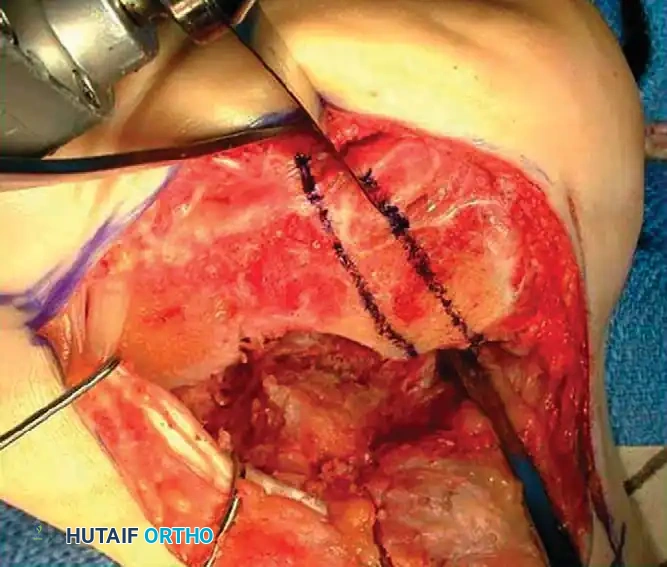

2. Calcaneal Osteotomy and Realignment Arthrodesis (Type II & III)

For severe deformities with loss of heel height and subtalar arthrosis, a distraction bone-block arthrodesis is indicated.

Intraoperative marking of the planned calcaneal osteotomy lines to correct varus/valgus malalignment.

Levering and distraction of the osteotomy site to restore calcaneal height and correct the talar declination angle.

The technique involves a lateral decompression, medial subtalar capsulotomy, and aggressive distraction of the subtalar joint. A lamina spreader is inserted to restore the talocalcaneal height.

A tricortical iliac crest bone graft (or the resected lateral wall exostosis) is fashioned into a tapered wedge and impacted into the distracted subtalar joint. This bone block restores heel height, improves talar inclination, and corrects varus/valgus malalignment.

Surgical Warning: The use of structural allografts in subtalar bone block arthrodesis has been associated with significantly higher nonunion rates compared to autograft. Autogenous bone is strongly recommended.

Fixation and Radiographic Confirmation

Rigid fixation is typically achieved with large-diameter (6.5mm or 7.3mm) cannulated cancellous screws placed from the posterior calcaneal tuberosity into the talar body and neck.